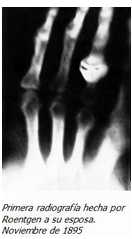

Descubrimiento de los rayos X

realizaba experimentos con tubos de vacío y un generador eléctrico. Con el hallazgo de este haz de luz capaz de atravesar la materia, nació el diagnóstico médico por imágenes que mejoró considerablemente el ejercicio de la medicina.

Se realizo su primera demostración de los rayos X el 23 de enero de 1896, ante la Sociedad Medica Física de Wurzburg,

El artista inglés Robert Alan Thom (1915-1979) pintó un cuadro en 1966 mostrando a Röntgen durante su primera demostración pública y a Albert von Kölliker poniendo su mano sobre una placa fotográfica para obtener una radiografía. La pintura se publicó en un libro titulado Grandes Momentos en Medicina por Parke, Davis & Company